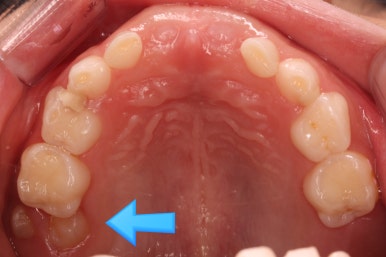

7개월 뒤 사진입니다.

해당 부위 어금니가 약간 나왔씁니다. 가장 간단하게 치료를 할 수 있는 상황이 되었네요.

어금니 방향이 서서히 변해가는 것을 보실 수 있을 것입니다.

단 3개월만에 제대로 못나오던 어금니 위치가 바로 잡혔습니다.

왼쪽이 부산어린이치아교정 키다리아저씨치과에서 치료하기 전 사진, 오른쪽이 후 사진입니다.

어금니가 잘 나온것을 확인할 수 있습니다.